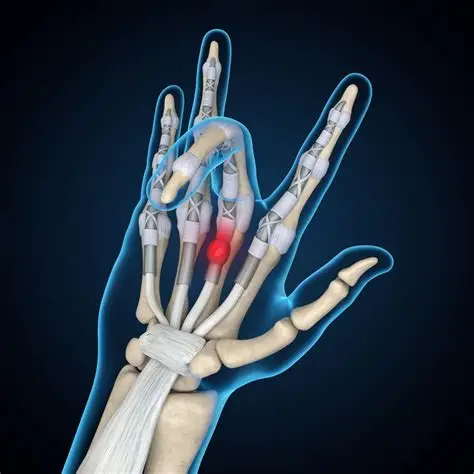

Trigger Finger

Carpal Tunnel Syndrome

Rheumatoid Arthritis

Ganglion Cyst

De Quervain's Tenosynovitis